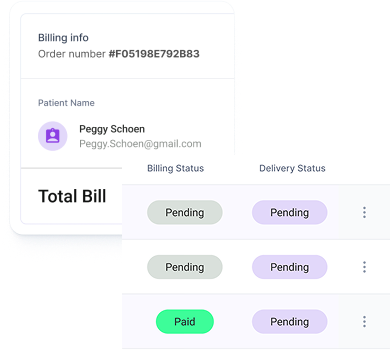

Monitor the journey of your prescriptions from being sent to awaiting payment, awaiting dispensing and dispatched

Prescription tracking

Monitor the journey of your prescriptions from being sent to awaiting payment, awaiting dispensing and dispatched